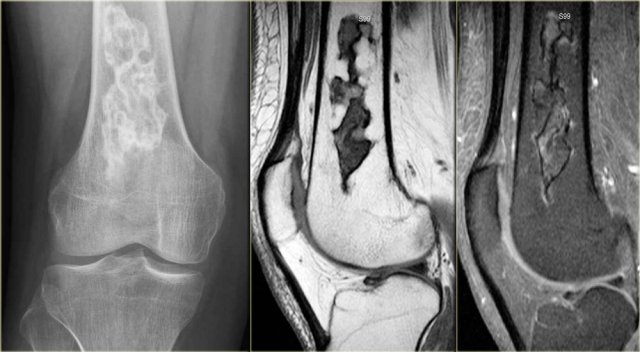

ABC (8)

On the left another ABC, located in the distal femur.

The plain radiograph shows a layered periosteal reaction and Codman triangle in direct relationship to an expansile lytic lesion with a thin peripheral bone shell.

CT also reveals the subperiosteal origin of the lesion with secondary involvement of the cortical bone.

Axial T2-weighted image with fatsat and contrast enhanced T1-weighted image with fat sat show multiple fluid-fluid levels with rim enhancement of the cavities filled with blood.

This is typical for an aneurysmal bone cyst.